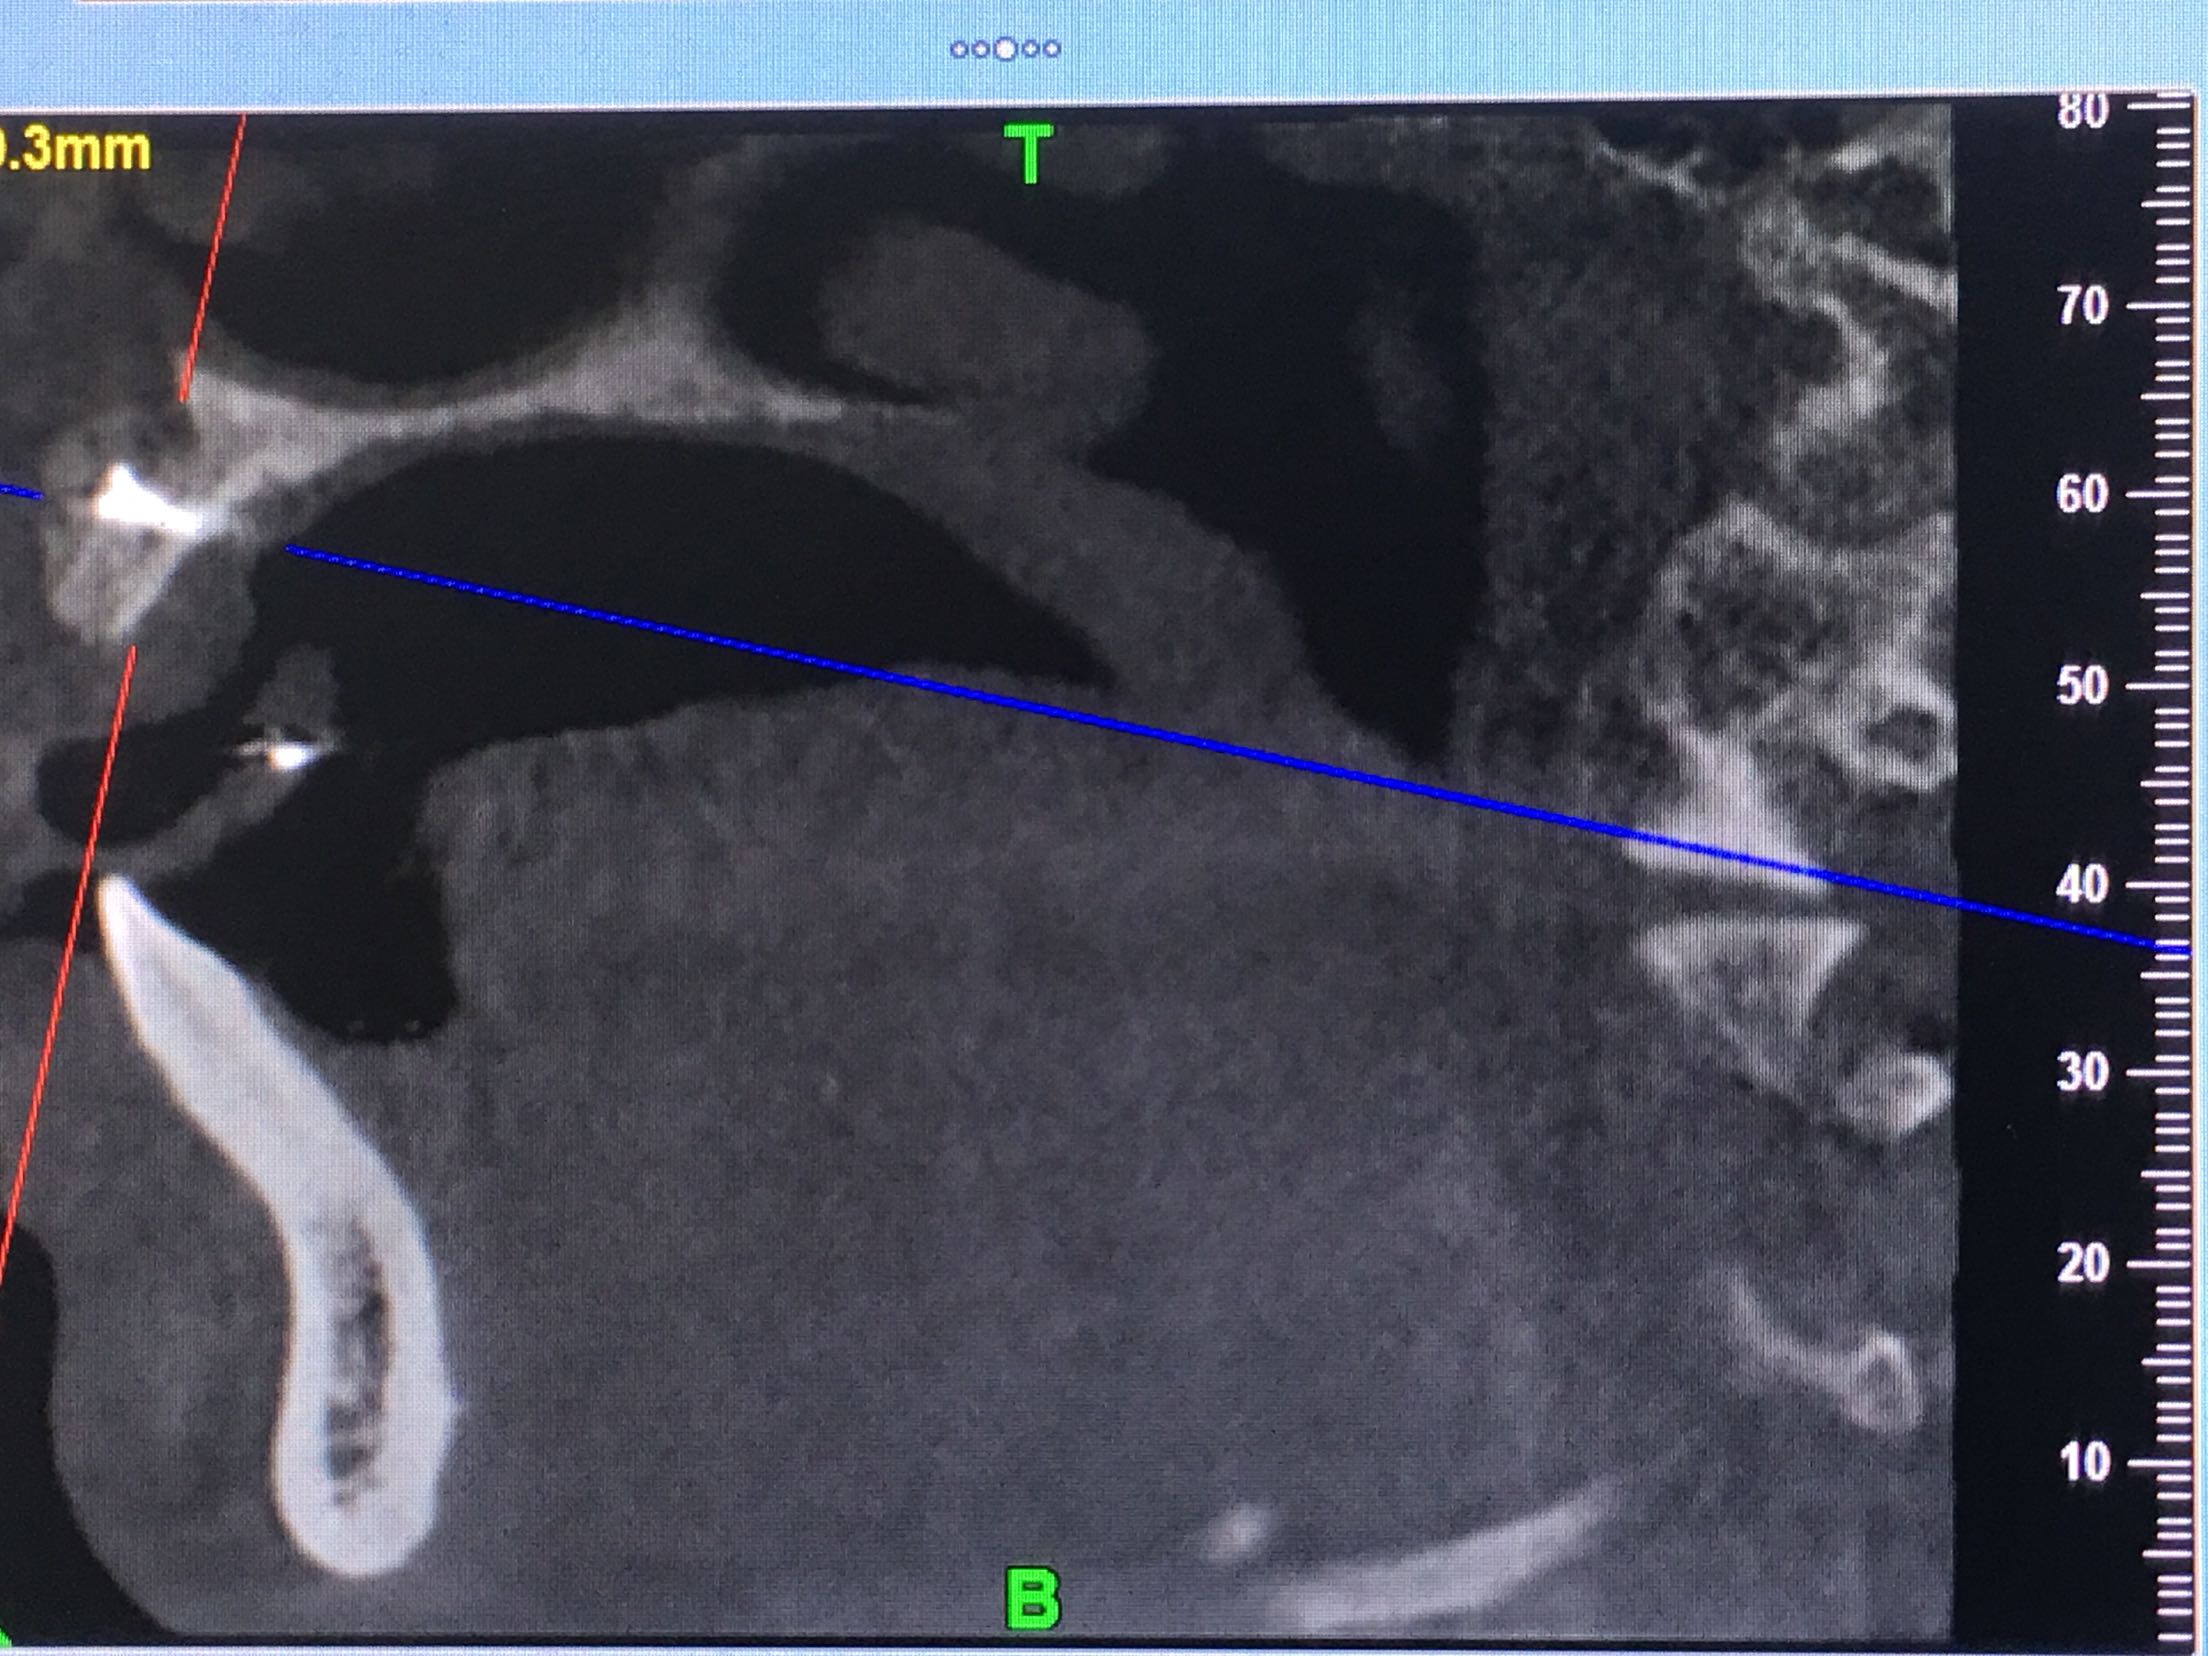

CBCT示11、12、21、22牙缺失,牙槽骨呈刀刃状,38、48牙阻生。

38、48牙超刀拔除,取双侧骨块,11、12、21、22梯形切口切开、翻瓣,切断粘骨膜松弛,骨块钛钉固定唇侧,植入Bio-ss骨粉0.5g,覆盖生物膜,严密缝合!嘱半年后种植!